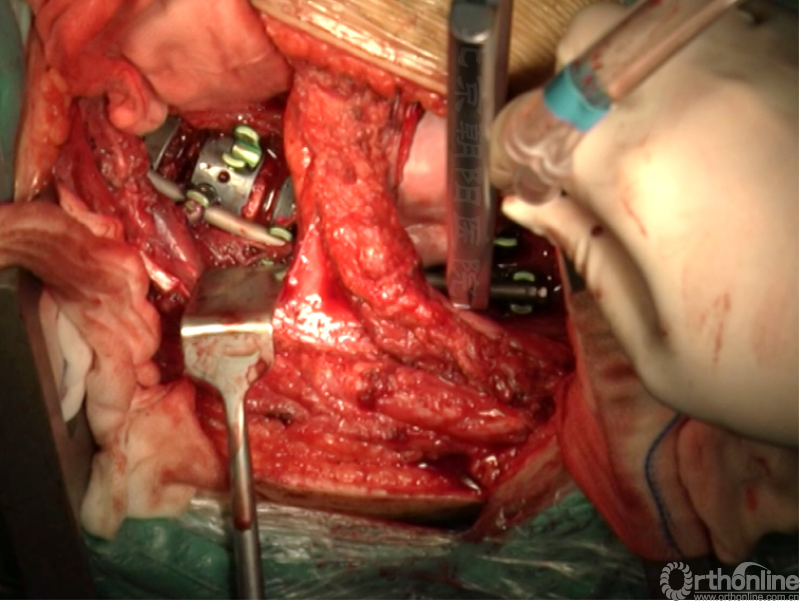

胸腰段/腰段AIS前路矫正手术示例

患者11岁青少年女性,诊断为Lenke 5C型AIS,T10-L4 Cobb角50.5°、T5-10 Cobb角31.5°,主弯顶椎为L1,融合范围选择为T1-L3。

术者:首都医科大学附属北京朝阳医院骨科 海涌教授

经近端需内固定的椎体(T11)相对应的肋骨表面做一弧形切口,分离浅层软组织直至肋骨表面的多层肌肉组织,切口止于脐的远端偏外侧。

骨膜下环形剥离完整显露肋骨。

切开第11肋骨肋软骨的连接部,并将肋骨靠近脊柱的部位切断。

同理将第12肋骨摘除。

由第12肋前端软骨部位进入腹膜后间隙,可以见腹膜后脂肪。

经腹壁和横膈下方钝性分离腹膜内组织。

切开横膈进入胸腔侧,术中由双肺呼吸改为凹侧单肺呼吸。

沿脊柱表面纵行切开腹膜,显露腹腔侧,注意避免伤及节段性血管。

在术中神经检测下逐个结扎切断节段动脉,术中注意监测脊髓供血情况。

切开纤维环,去除终板椎间盘组织,直至纤维环的后侧边缘,对于严重侧凸如果需要可至后纵韧带。

进一步使用刮匙和髓核钳完整去除椎间盘组织和终板,营造植骨面。

内固定选择的是5.5mm双棒系统,先置入顶椎的螺钉垫板。

置入顶椎的椎体螺钉,螺钉可置入椎体中部到后方1/3之间的范围内。

使用双棒系统时,先置入背侧的螺钉,螺钉指向椎体中线,后置入腹侧的螺钉,螺钉轻度指向后侧。形成对椎体的三角形抓持力。

胸腔侧、腹腔侧螺钉全部置入后,骨移植物植人的越靠近后纵韧带或者纤维环的后缘越好。

将预先折弯的金属棒先置入背侧。

椎间融合器经前方置入凹侧,确保腰椎前凸的恢复和冠状面畸形的矫正,将剩下的骨移植物置入椎间隙内。

置入腹侧金属棒。

使用双棒系统时先安装背侧的棒,可进行90°的去旋转,也可以直接通过前方螺钉矫正冠状面和矢状面的畸形,然后固定后方的棒,可进一步通过加压矫正冠状面畸形。

矫正后神经检测未见异常术中唤醒患者下肢活动良好,术中透视矫正效果满意、内固定位置良好。根据手术具体情况放置合适尺寸的横连接加强内固定。

尽量多的闭合胸膜,紧密缝合横膈。

分别缝合第11、12肋骨的骨膜。

留置合适直径的胸腔闭式引流管,根据术中情况选择是否放入腹腔引流。逐层缝合腹壁,逐层缝合皮下组织和皮肤。